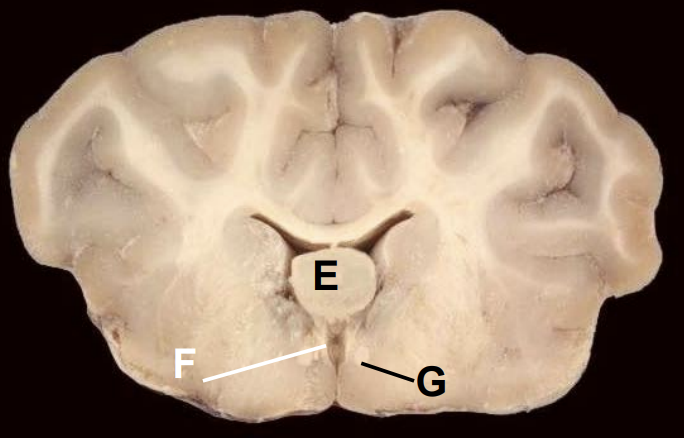

5

Q

E

A

Thalamus

6

F

Third ventricle

7

G

Fornix